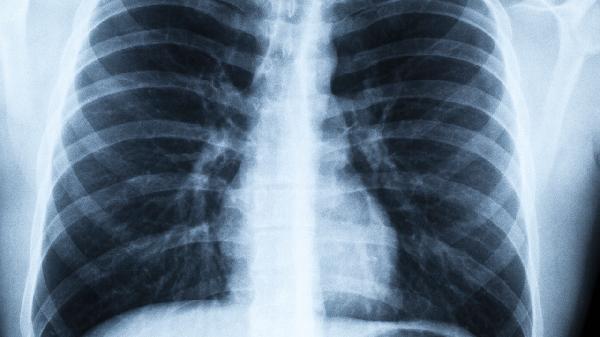

被诊断出肺炎可能由细菌感染、病毒感染、支原体感染或吸入性因素引起,常见症状包括咳嗽、发热、胸痛和呼吸困难,需根据...